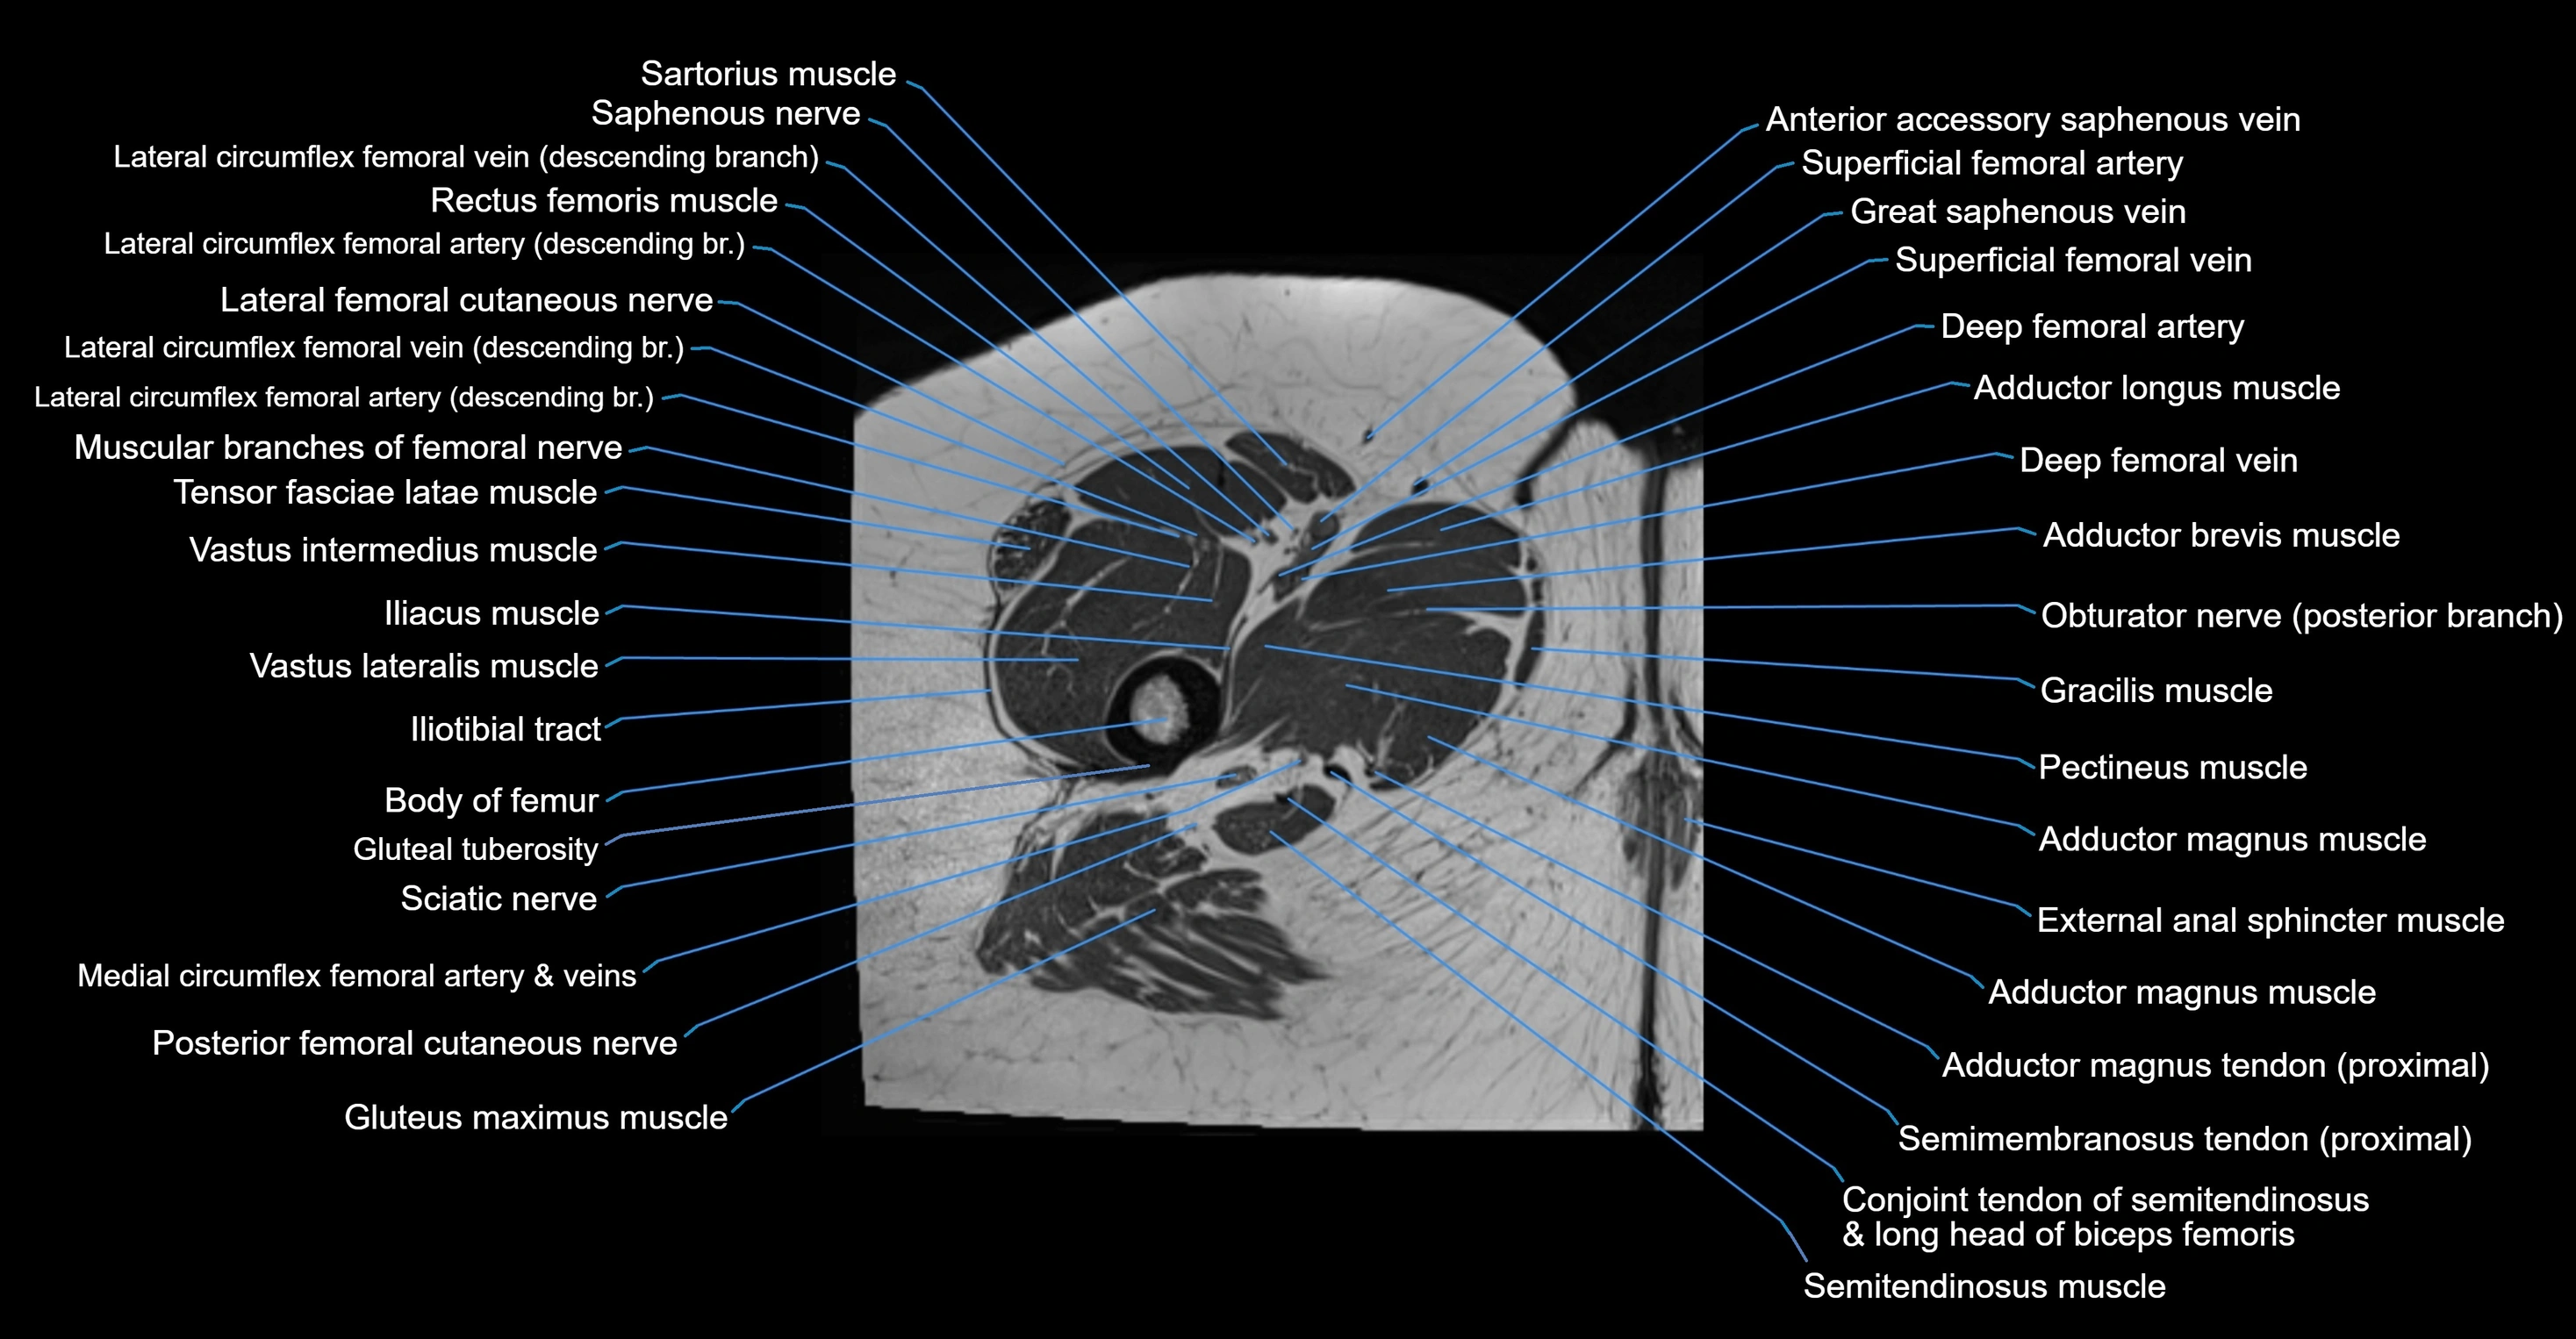

- Adductor brevis muscle

- Adductor longus muscle

- Adductor magnus muscle

- Body of femur

- Conjoint tendon of biceps femoris & semitendinosus

- Deep femoral artery (profunda femoris)

- Deep femoral vein (profunda femoris vein)

- Femoral nerve

- Gluteal tuberosity

- Gluteus maximus muscle

- Gracilis muscle

- Iliotibial tract

- Lateral circumflex femoral artery

- Lateral circumflex femoral veins

- Lateral femoral cutaneous nerve

- Medial circumflex femoral artery

- Medial circumflex femoral vein

- Muscular branches of femoral nerve

- Pectineus muscle

- Posterior femoral cutaneous nerve

- Rectus femoris muscle

- Saphenous nerve

- Sartorius muscle

- Semimembranosus tendon (proximal)

- Superficial femoral artery

- Tensor fasciae latae muscle

- Vastus intermedius muscle

- Vastus lateralis muscle

- Vastus medialis muscle